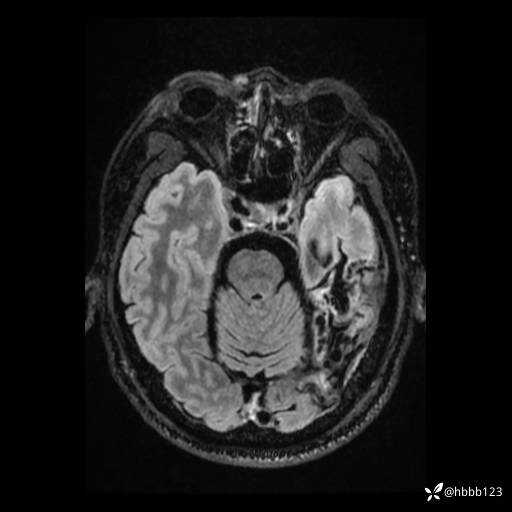

患者男,43岁。

简要病史:癫痫患者复诊,昨日发作5-6次,建议住院进一步治疗。

入院完善脑癫痫组合序列:

T2: